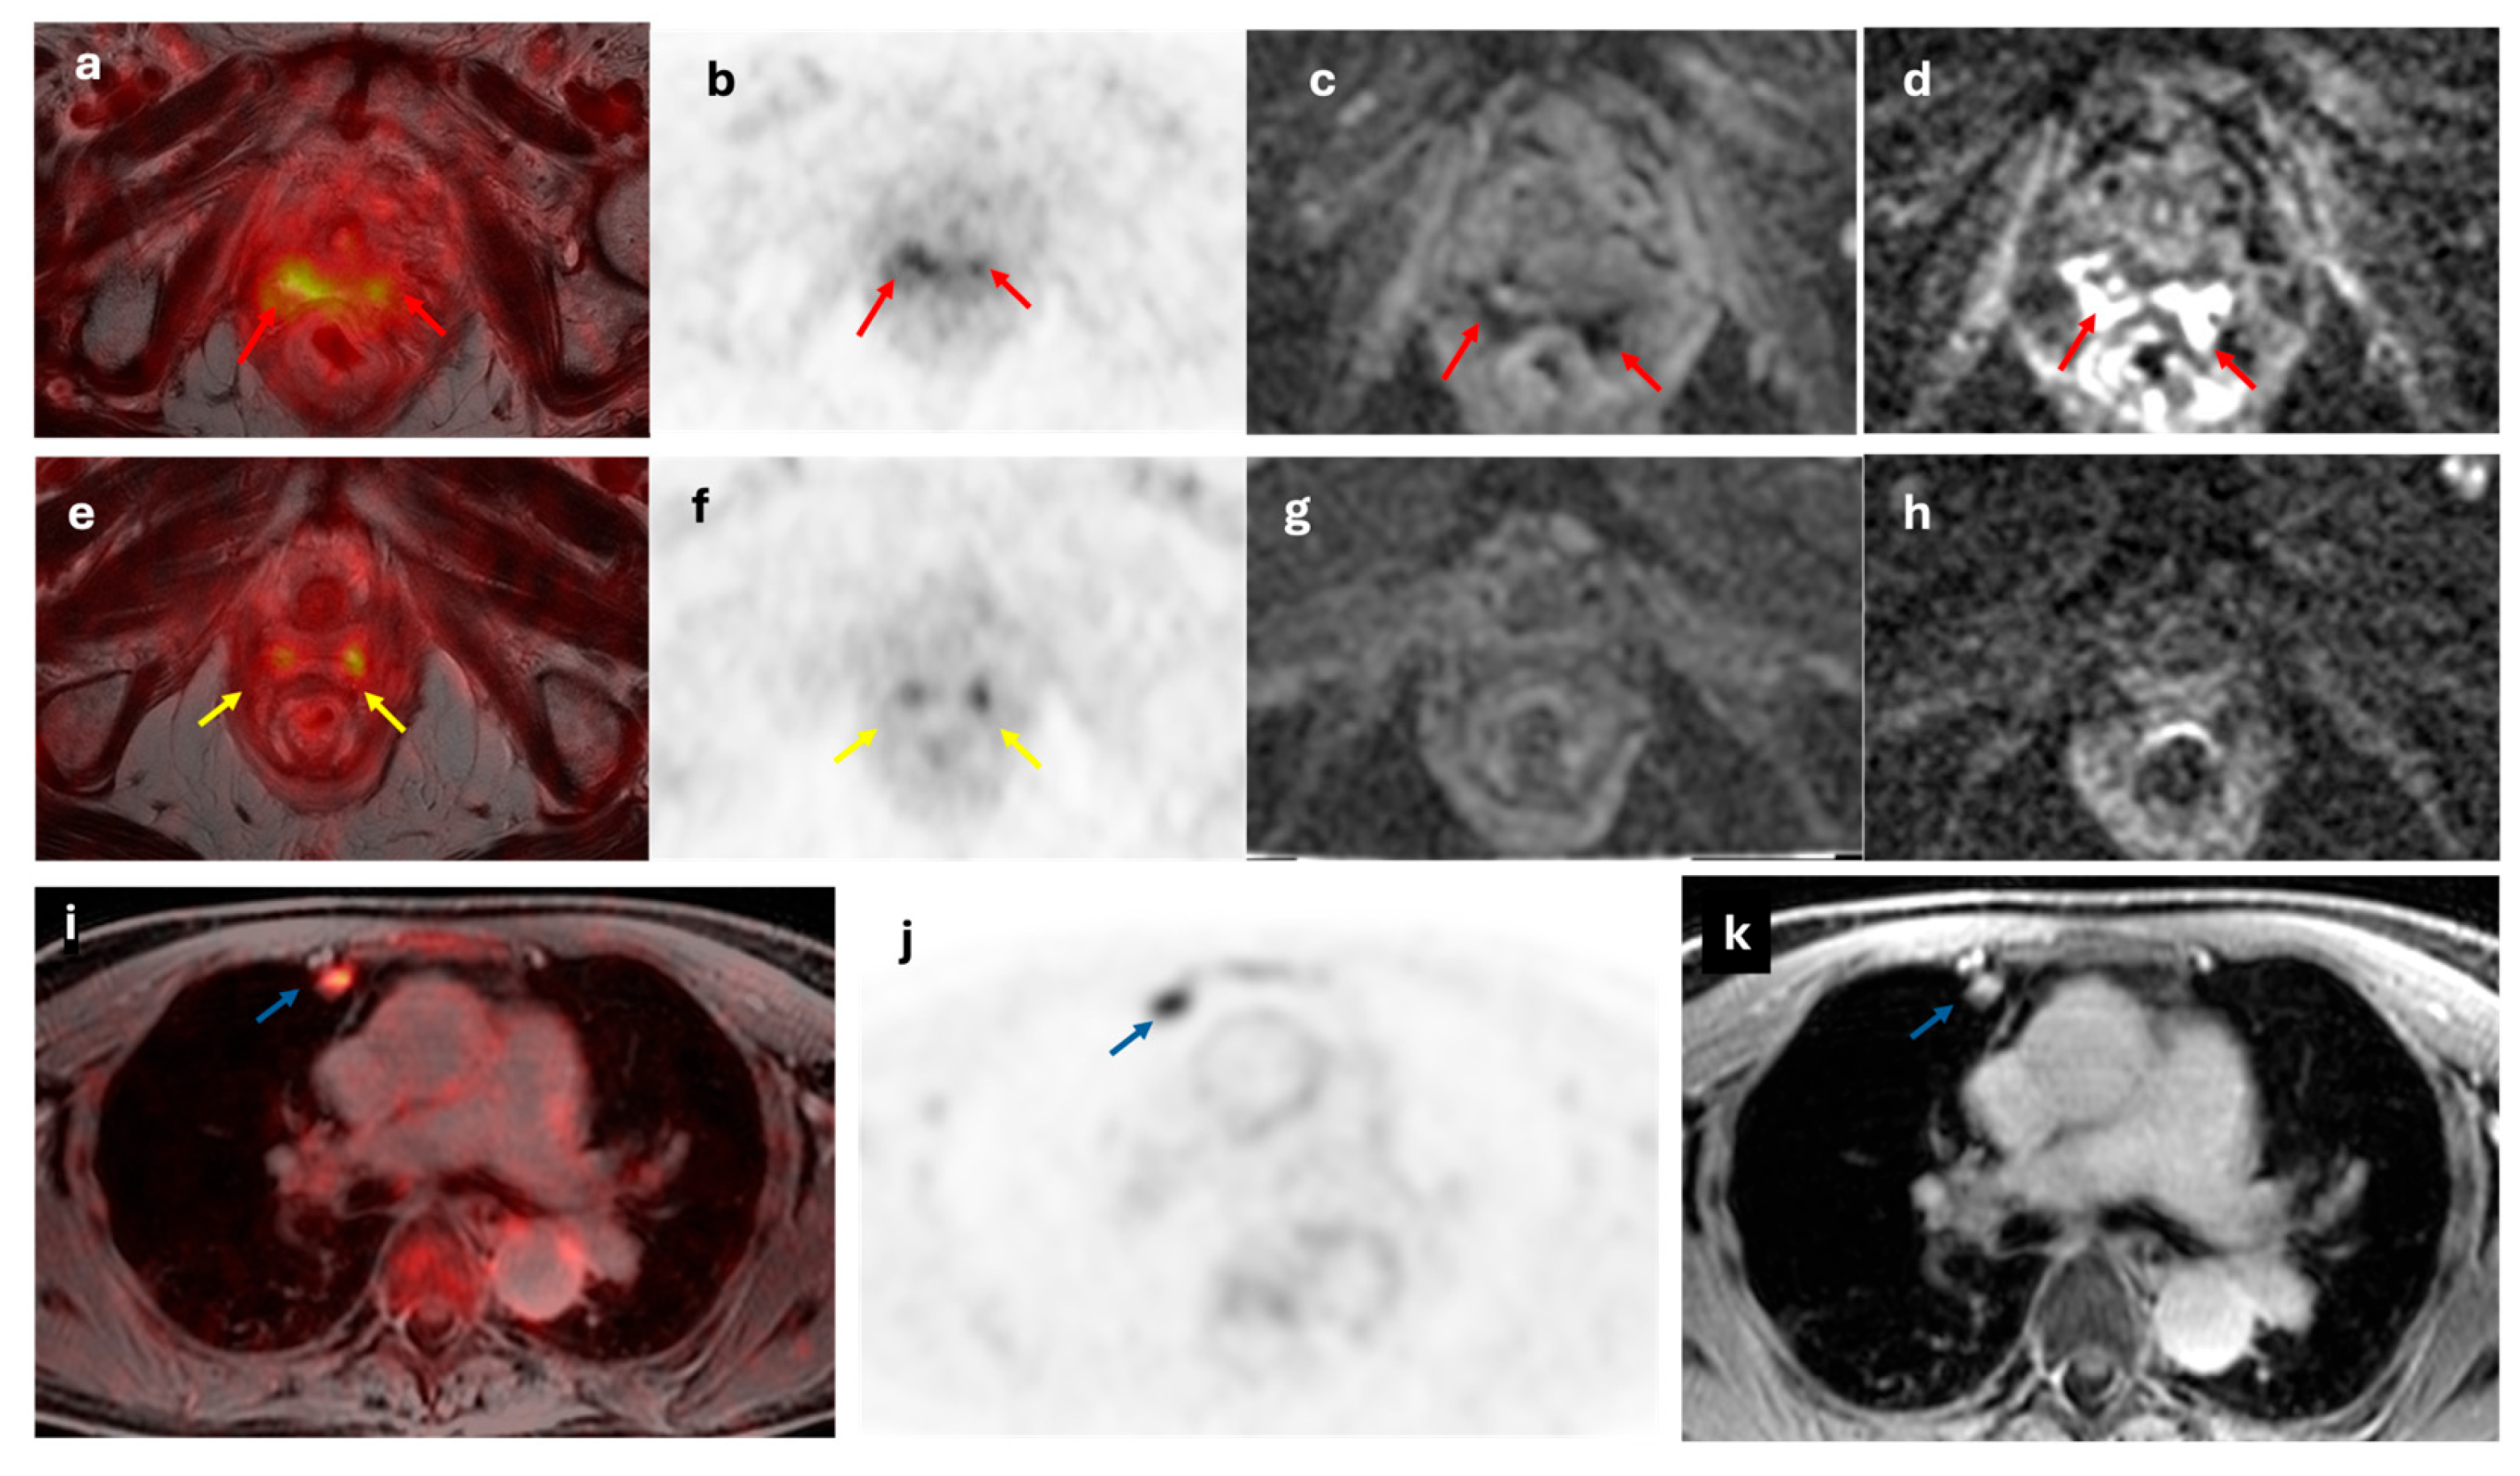

- Bian, L.; Wang, M.; Gong, J.; Liu, H.; Wang, N.; Wen, N.; Fan, W.; Xu, B.; Wang, M.; Ye, M.; et al. Comparison of Integrated PET/MRI with PET/CT in Evaluation of Endometrial Cancer: A Retrospective Analysis of 81 Cases. PeerJ 2019, 7, e7081. [CrossRef]

- Ironi, G.; Mapelli, P.; Bergamini, A.; Fallanca, F.; Candotti, G.; Gnasso, C.; Taccagni, G.L.; Sant’Angelo, M.; Scifo, P.; Bezzi, C.; et al. Hybrid PET/MRI in Staging Endometrial Cancer: Diagnostic and Predictive Value in a Prospective Cohort. Clin Nucl Med 2022, 47, e221–e229. [CrossRef]

- Yu, Y.; Zhang, L.; Sultana, B.; Wang, B.; Sun, H. Diagnostic Value of Integrated 18F-FDG PET/MRI for Staging of Endometrial Carcinoma: Comparison with PET/CT. BMC Cancer 2022, 22, 947. [CrossRef]

- Bezzi, C.; Zambella, E.; Ghezzo, S.; Fallanca, F.; Samanes Gajate, A.M.; Franchini, A.; Ironi, G.; Bergamini, A.; Monaco, L.; Evangelista, L.; et al. 18F-FDG PET/MRI in Endometrial Cancer: Systematic Review and Meta-Analysis. Clin Transl Imaging 2022, 10, 45–58. [CrossRef]

- Weissinger, M.; Bala, L.; Brucker, S.Y.; Kommoss, S.; Hoffmann, S.; Seith, F.; Nikolaou, K.; la Fougère, C.; Walter, C.B.; Dittmann, H. Additional Value of FDG-PET/MRI Complementary to Sentinel Lymphonodectomy for Minimal Invasive Lymph Node Staging in Patients with Endometrial Cancer: A Prospective Study. Diagnostics (Basel) 2024, 14, 376. [CrossRef]

- Nie, J.; Zhang, J.; Gao, J.; Guo, L.; Zhou, H.; Hu, Y.; Zhu, C.; Li, Q.; Ma, X. Diagnostic Role of 18F-FDG PET/MRI in Patients with Gynecological Malignancies of the Pelvis: A Systematic Review and Meta-Analysis. PLoS One 2017, 12, e0175401. [CrossRef]

- Kirchner, J.; Sawicki, L.M.; Suntharalingam, S.; Grueneisen, J.; Ruhlmann, V.; Aktas, B.; Deuschl, C.; Herrmann, K.; Antoch, G.; Forsting, M.; et al. Whole-Body Staging of Female Patients with Recurrent Pelvic Malignancies: Ultra-Fast 18F-FDG PET/MRI Compared to 18F-FDG PET/CT and CT. PLoS One 2017, 12, e0172553. [CrossRef]

- Zheng, M.; Xie, D.; Pan, C.; Xu, Y.; Yu, W. Diagnostic Value of 18F-FDG PET/MRI in Recurrent Pelvis Malignancies of Female Patients: A Systematic Review and Meta-Analysis. Nucl Med Commun 2018, 39, 479–485. [CrossRef]

- Sawicki, L.M.; Kirchner, J.; Grueneisen, J.; Ruhlmann, V.; Aktas, B.; Schaarschmidt, B.M.; Forsting, M.; Herrmann, K.; Antoch, G.; Umutlu, L. Comparison of 18F–FDG PET/MRI and MRI Alone for Whole-Body Staging and Potential Impact on Therapeutic Management of Women with Suspected Recurrent Pelvic Cancer: A Follow-up Study. Eur J Nucl Med Mol Imaging 2018, 45, 622–629. [CrossRef]